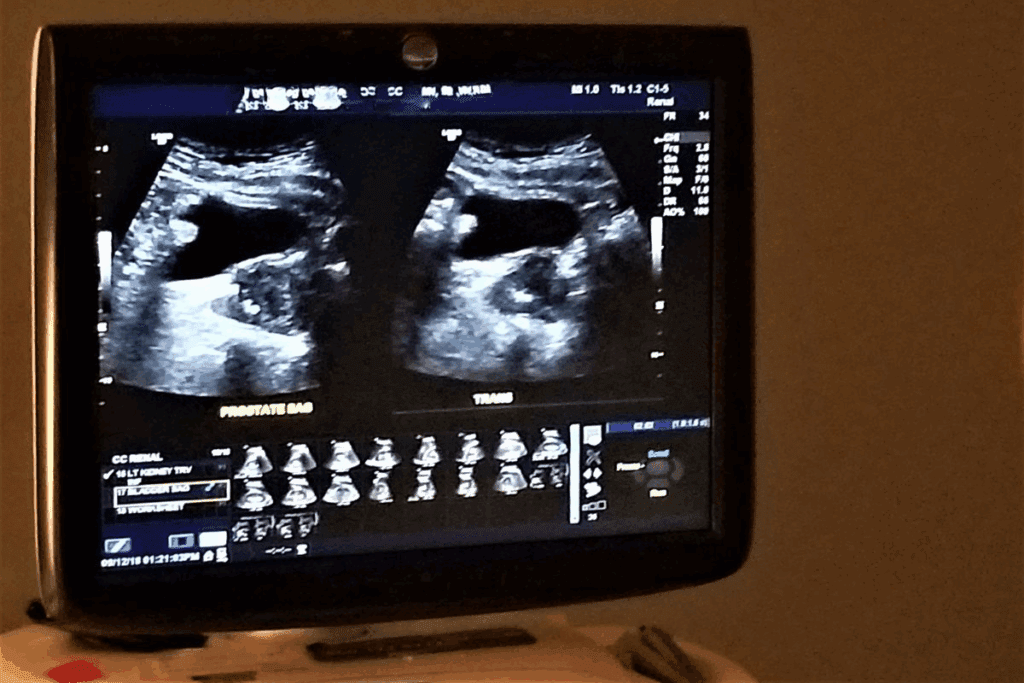

Essential Blood and Urine Tests for Diagnosis

Diagnosing kidney disease needs blood and urine tests. The serum creatinine test checks for creatinine, a waste product. The estimated Glomerular Filtration Rate (eGFR) test shows kidney function based on creatinine, age, and sex.

Urine tests, like urinalysis, look for protein or blood in the urine. The urine albumin-to-creatinine ratio test finds albumin, showing kidney damage.